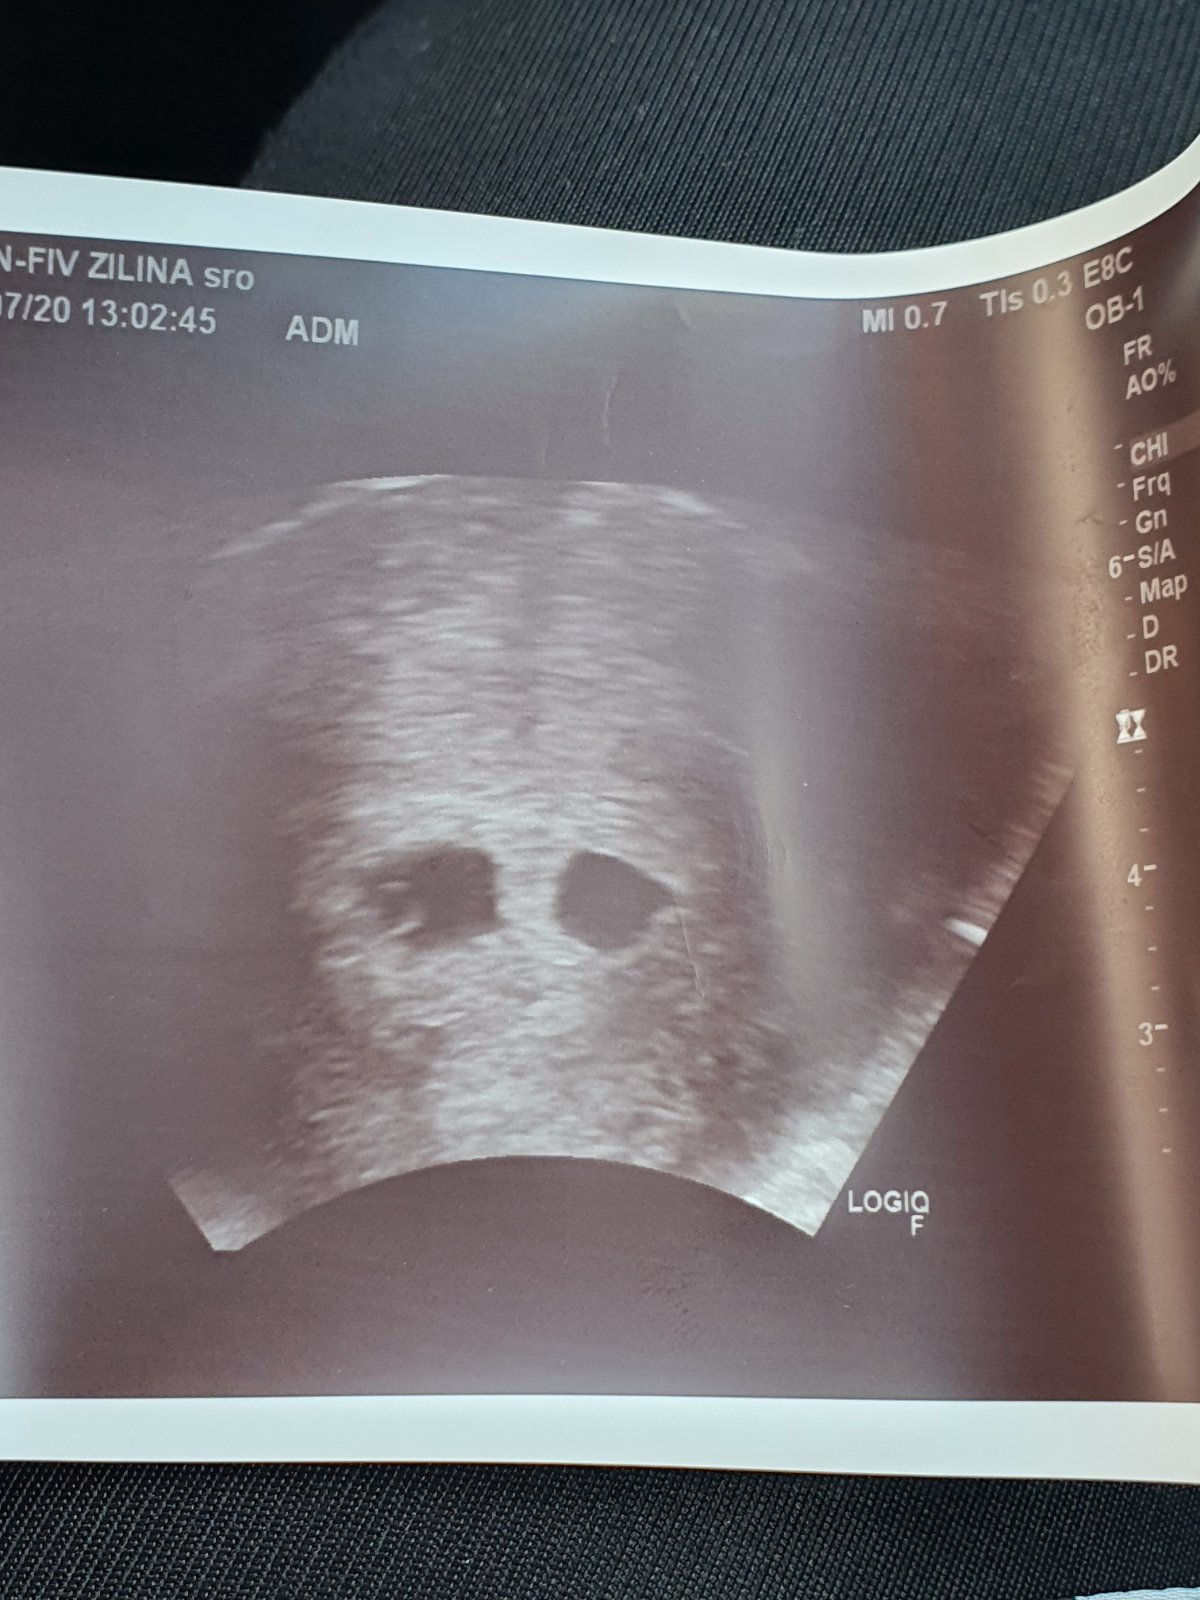

Ahojte dievcata, planujete aj tento mesiac dalsi pokus IUI? Ja som skusila so stimulaciou, ale narastol jeden 31mm, tak mam strach, ze to bude cysta.

ahojte, tak ja som v stredu pred tyzdnom absolvovala 2. pokus. Druhykrat po sebe sa mi vytvorili folikuly na spravnej strane (mam len jeden vajcovod), tak nastastie mi to mohli urobit. Problem bol, ze jeden mal 32mm, co je zda sa prilis vela a druhy 17mm, co jej zas asi malo. Je to tyzden a vobec nic necitim :( Ale cez vikend asi skusim testovat. Tebe @dzankah blahozelam a @teav drzim palce 🙂